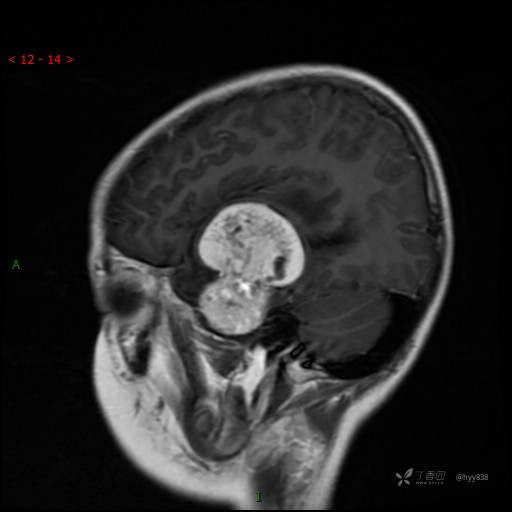

“典藏”病例分享。10岁儿童,头痛头晕一周余,CT、MRI 都有---结果公布~

患者年龄:10岁

主诉:头痛头晕一周余

简要病史:患者于一周前无明显诱因开始出现头痛头晕,无恶心呕吐,无肢体抽搐,无寒颤高热,无腹胀腹泻,无视力下降及视野缺损,上述症状休息后可稍缓解,未引起重视。 2天前患者头痛头晕不适加重,伴有恶心感,无呕吐,遂到当地人民医院行头颅CT检查示:左侧颞部占位性病变,今日家属为求进一步治疗,来我院门诊求治。门诊拟“左侧颞部占位性病变”收入我科。 患病以来,患者精神、饮食、睡眠尚欠佳,大小便如常,体力体重无明显变化。

临床诊断:左侧颞部占位

MRI增强